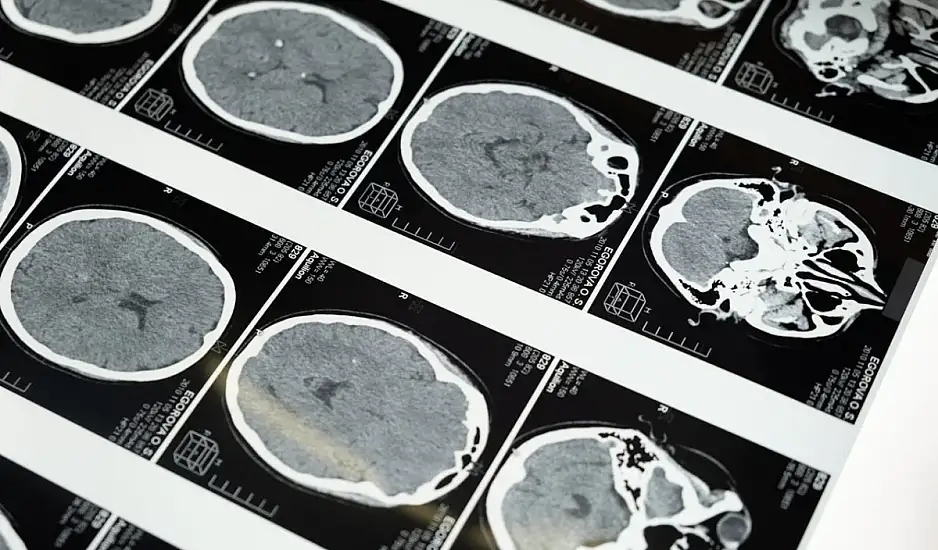

Οι τύποι εγκεφαλικών: Ισχαιμικό και αιμορραγικό

Ο Δρ Mandell αναλύει τους δύο τύπους εγκεφαλικών:

Ισχαιμικό Εγκεφαλικό: Αποτελεί το 87% των περιπτώσεων και προκαλείται από θρόμβο που φράζει αιμοφόρο αγγείο προς τον εγκέφαλο.

Αιμορραγικό Εγκεφαλικό: Προκαλείται από αιμορραγία λόγω ρήξης αρτηρίας ή ανευρύσματος, που ασκεί πίεση στον εγκέφαλο.

Και οι δύο τύποι οδηγούν σε απώλεια εγκεφαλικών λειτουργιών, και η άμεση ανταπόκριση είναι καθοριστική.